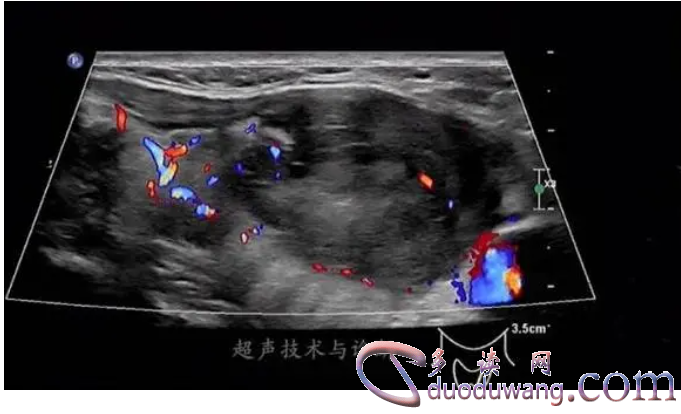

我们来了解一下什么是高回声和低回声。高回声通常指的是在成像图像中显现为白色区域的区域,其表示该区域比周围组织更加密集,且反射声波的能力更强。相反,低回声通常看起来像黑色区域,表示该区域比周围组织更松散或在该区域内有更多的液体存在,能够更好地吸收声波。

另一方面,低回声也可以作为疾病的提示标志。例如,在心肌超声中,低回声区域可以表示心脏内有积液。在甲状腺乳头状癌的超声显像中,液性物质就很容易被检测出来,所以低回声就成了该疾病的征象之一。